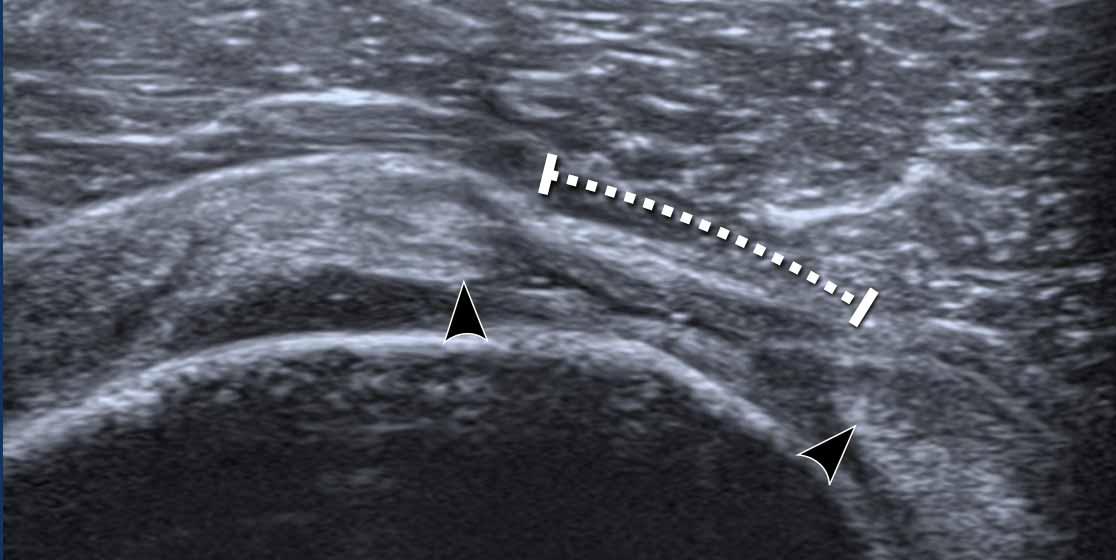

Full thickness tears

Hình ảnh này cho thấy rách hoàn toàn toàn bộ chiều dày gân cơ trên gai.

Có một ổ dịch giảm âm nhỏ.

Cả hai đầu gân đều tù và co rút (đầu mũi tên).

Đây là một ví dụ khác về rách toàn bộ chiều dày gân cơ trên gai.

Khoảng trống được lấp đầy bởi một ít dịch từ khớp ổ chảo-cánh tay (mũi tên)